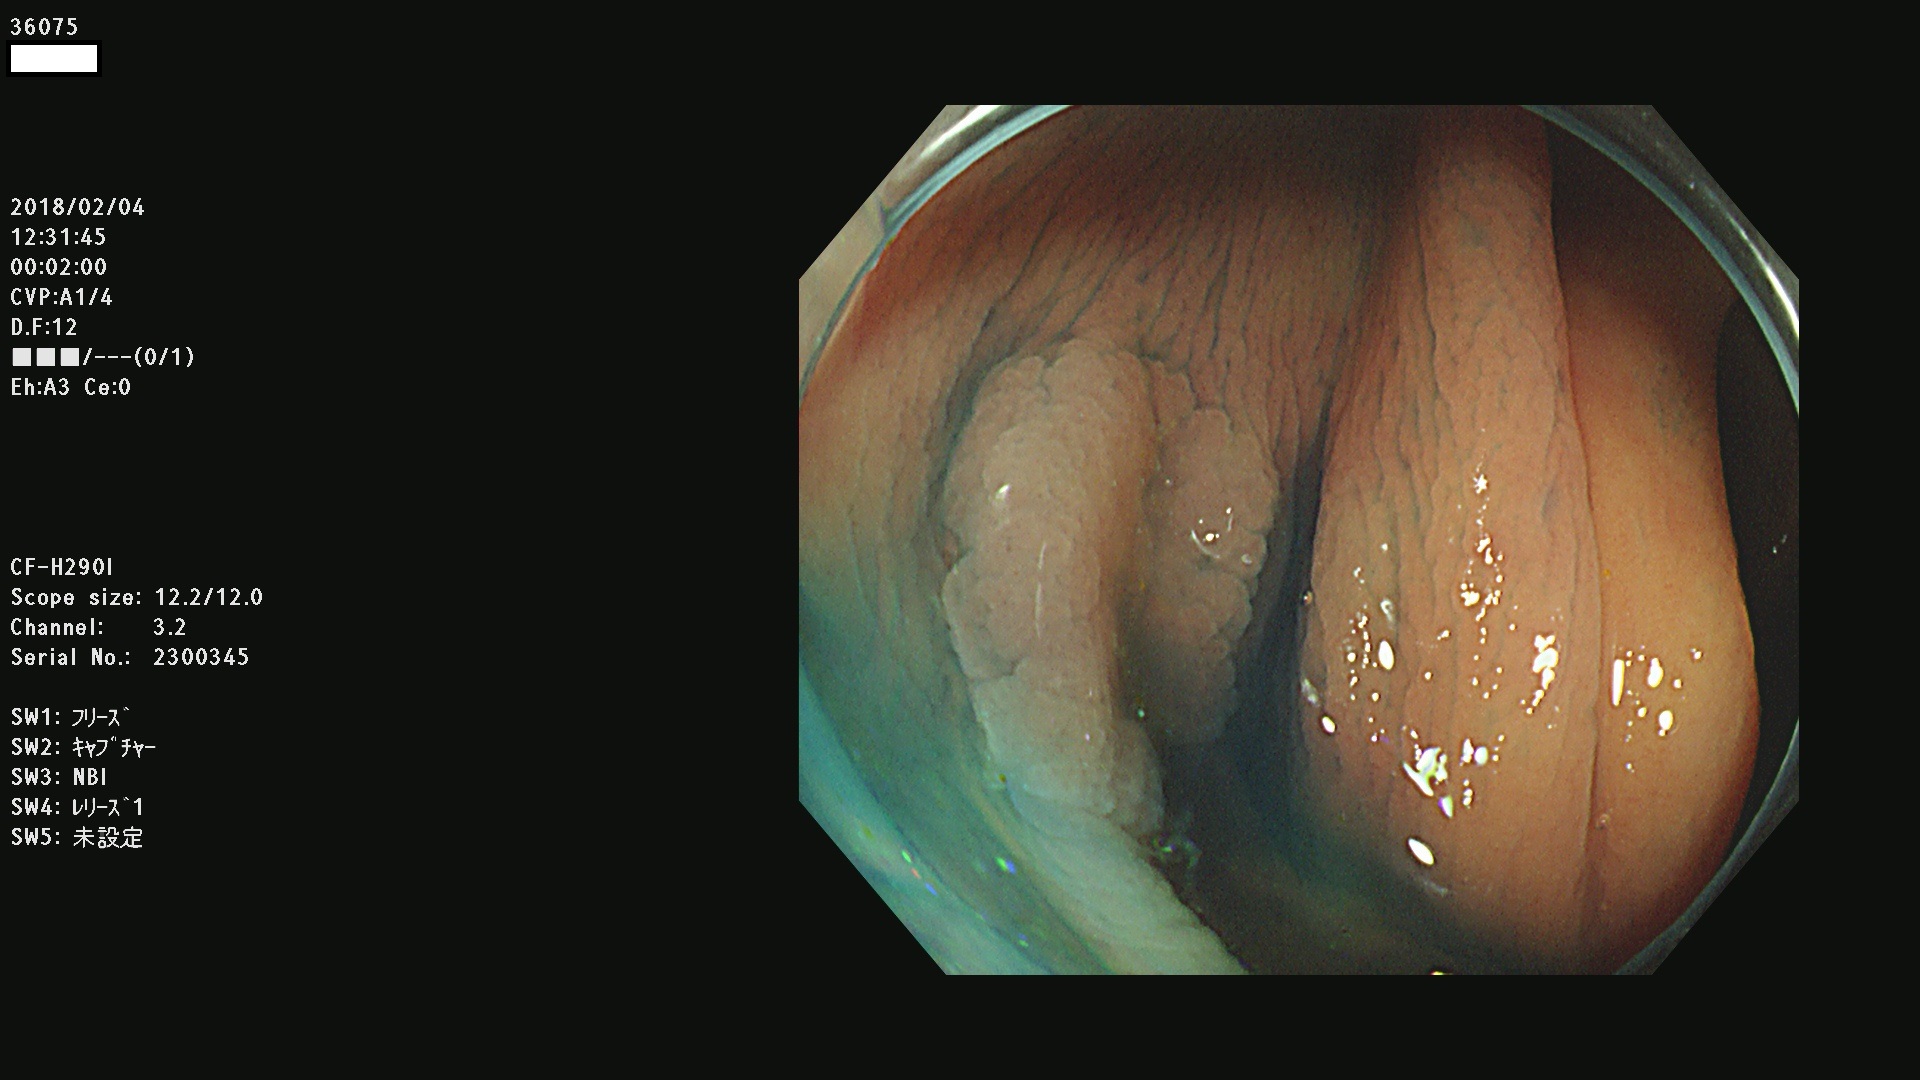

36000 36001 36003 36004 36008 36009 36012 36013(SSA/Pのみ) 36015 36016 36017 36021 36022 36023 36027 36030 36033(SSA/Pのみ) 36036 36037 36042 36044 36045 36046 36047 36051 36053 36054 36055 36056 36057 36058 36059 36060 36061 36062 36073(SSA/Pのみ) 36074 36075 36076 36078 36081 36082 36083 36089 36090(SSA/Pのみ) 36094 36096

発見困難で危険性の高い平坦型病変(上記100名より抽出)